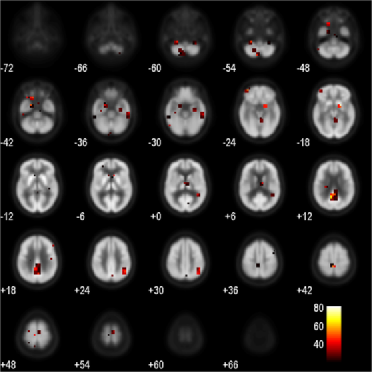

Refer to caption

Figure 5: Clusters of voxels identified using our approach for the ADNI data.

Second, we investigate the voxels that are selected by our method. We use 5-fold cross-validation to the full data set to choose the optimal set of tuning parameters. The identified clusters of voxels [β^(u,v,w)0^𝛽𝑢𝑣𝑤0\hat{\beta}(u,v,w)\neq 0] are shown on selected axial slices in Figure 5, which are presented from the bottom of the brain to the top. The clusters of voxels with hot colors show a positive association to prediction of MMSE scores, whereas those with cold colors show a negative association. Each small square represents a small cluster of voxels. To assess the significance of the selected voxels, similar to what we have done in simulation studies, we permute the response variable MMSE score 200 times. It turns out that 95.3% of the selected voxels are significant at the 5% level. In addition to this pointwise testing, we also consider the global test described by Nichols and Holmes (2001), which provides a way to control the family-wise error rate by comparing β^(tj)^𝛽subscript𝑡𝑗\hat{\beta}(t_{j}) to a “maximal statistic.” It turns out that only 15.6% of the selected voxels are significant at the 5% level, which is more conservative than the pointwise testing procedure. To further evaluate the stability of the selection, we generate 100 bootstrap samples and for each bootstrap sample, we apply our method including the tuning parameter selection via 5-fold cross-validation. Similar approaches also have been employed by other researchers, such as Sauerbrei and Schumacher (1992), Royston and Sauerbrei (2008) and Meinshausen and Bühlmann (2010). To summarize the results, we count the number of times that each voxel is selected over 100 bootstrap samples and denote it as the bootstrap inclusion frequency (BIF). The voxel BIFs are presented in Figure 6. The locations of these more frequently selected voxels are also presented in the 3D sagittal view in Figure 7 for ease of understanding. It can be seen that the highly selected brain regions agree well with the results in Figure 5. We note that the clusters of voxels identified in our analysis shown in Figures 5 and 6 reveal high associations of the expected anatomical regions with cognitive deficits. For example, the orange ones on slices “++12” and “++18” in Figure 5 and the big cluster on the same slices in Figure 6 indicate that the posterior cingulate/precuneus cortex is significantly related to cognitive impairment; the blue ones on slices “-60,” “-54” and “-48” in Figure 5 and the clusters on the same slices in Figure 6 suggest that the medial temporal/hippocampal cortex is also closely involved; the red ones on slices “-42,” “-36” and “-30” in Figure 5 and the corresponding clusters on the same slices in Figure 6 correspond to the lateral temporal cortex. Many studies have demonstrated that the most prominent metabolic abnormalities are found in these regions; see, for example, Foster et al. (1984), Minoshima et al. (1995, 1997), Mueller et al. (2005). In our study, we have particularly found the most predictive voxels of the cognitive impairment in these regions. Other involved regions include the superior lateral parietal cortex and the frontal cortex, which are all known to be related to the progression of Alzheimer’s disease.